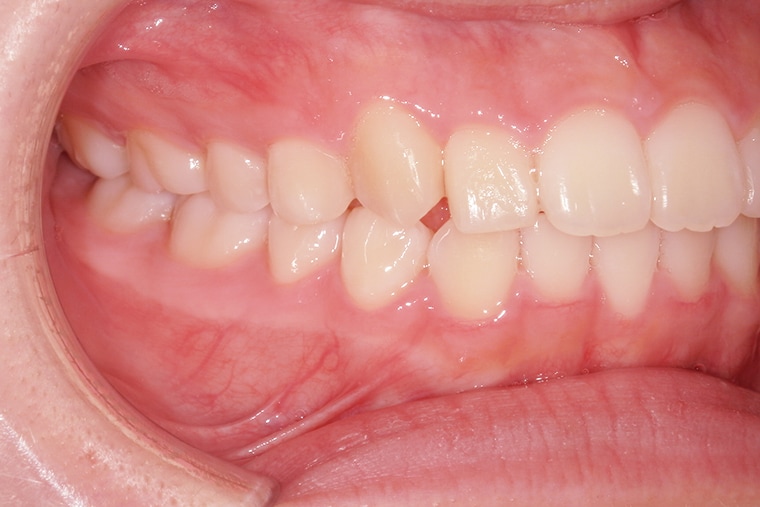

Case Study15歳女性出っ歯のマウスピース矯正-矯正期間10ヶ月

AFTER

約10ヶ月の矯正期間を経て、上の前歯の出っ歯は改善され、口を閉じることが自然にできるようになりました。歯並びが整ったことで笑顔に自信が持てるようになり、日常生活でも以前より表情が明るくなったのを感じます。学校生活や友達との会話でも、口元を気にすることが少なくなり、本人も嬉しそうです。